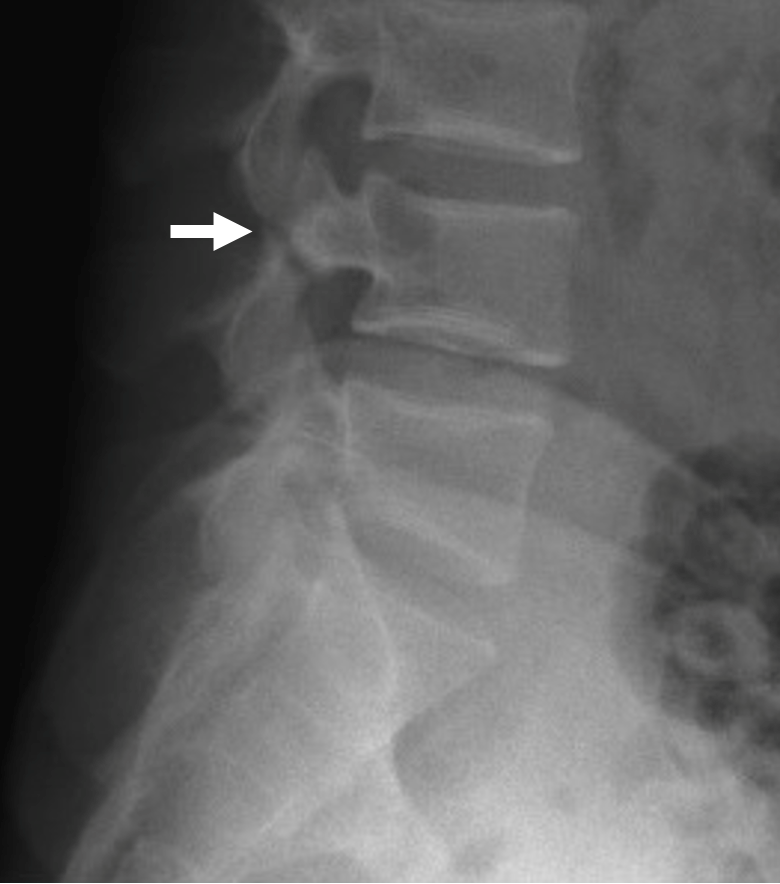

A 19-year-old, physically active male with no significant past medical history presented to the emergency department with worsening low back pain. He reported approximately one year of chronic, non-radiating pain that acutely worsened over the prior two weeks and was now limiting ambulation with an antalgic gait. He denied trauma, fever, bowel or bladder incontinence, paresthesia, or weakness. Over-the-counter analgesics provided only transient relief. On examination, he appeared well. Gait assessment confirmed an antalgic pattern. There was no midline spinal tenderness, deformity, or neurological deficit. Given the prolonged symptom duration and functional limitation, lumbosacral radiography was obtained, revealing a pars interarticularis defect at L4 consistent with spondylolysis (Figure 1). Conservative management with rest, analgesics, activity modification, and referral to physical therapy was initiated. A spine specialist referral was arranged from the ED for outpatient follow-up.

Figure 1. Lateral lumbosacral spine radiograph indicating a pars interarticularis defect at L4 (white arrow).

On oblique radiographs, the pars defect is classically visualized as a cortical defect in the "neck" of the Scottie dog sign, aiding rapid recognition and triage in acute care settings. In this case, an annotated lateral radiograph (Figure 1) indicates the L4 defect.